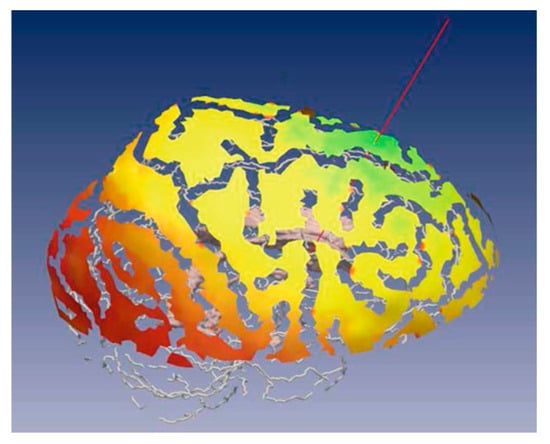

For path planners in minimally invasive procedures, the path planner should search for an appropriate entry point and an optimal trajectory. When the target is a single point and the tool is a straight, the path planning reduces to an entry point planner. Therefore, in the case of the straight needle, once the entry and target points are planned, the path is fully defined. For the straight needle scenario which covers the majority of the clinical procedures, the path planner could be developed to either output the best entry point on the skull or function as a decision-support system by visualizing color-coded regions on the skull labeled as “safe regions”, “low-risk regions”, and “high-risk regions”. This accessibility map could help guide neurosurgeons to manually select the entry point [,,,,,]. Figure 3 shows an example of accessibility map, with the green region labelling the safest region to plan the entry point. When the tool is curved, on the other hand, the path planner should plan the entry point as well as the curvilinear surgical tool trajectory to fully define a safe and optimal path to reach the desired target.

Figure 3.

Color map of soft constraint on the skull of a patient generated for guiding the neurosurgeon to select the best entry point. Green region are safe entry points, yellow region are entry points with moderate risk, are red region are high risk entry points and are No-Go points. Reprinted/adapted with permission from Ref. [].